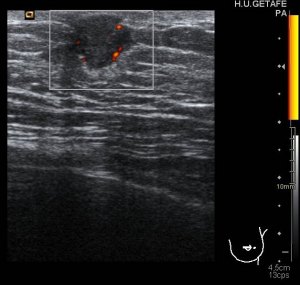

La imagen 5 y la imagen 6, sin y con doppler, para estudiar vascularización del tejido mamario patológico. No existe claro nódulo, por tanto no medimos. Por contra en la imagen 7,8 y 9 que te pongo a continuación puedes observar un claro nódulo retroareolar de la mama masculina, que tiene este aspecto semiológico: